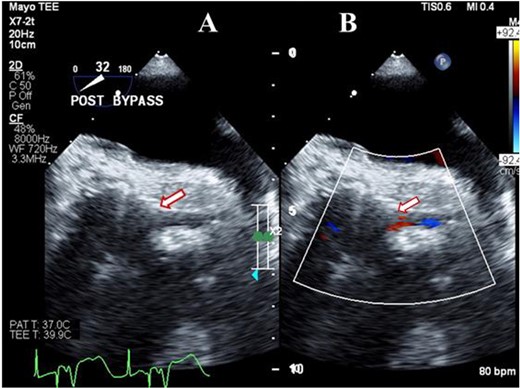

As the flow in LMCA was suboptimal, options of coronary artery bypass grafting (CABG) the left anterior descending (LAD) and obtuse marginal arteries vs Bentall were considered. As harvesting the conduits for CABG would have further prolonged duration of LV ischemia; Bentall operation was performed with a 23-mm On-X valved conduit on moderate hypothermic cardioplegic arrest. Patient was weaned-off CPB on minimal inotropes. TEE confirmed the patent LMCA (Fig. 2A) with laminar flow on color Doppler imaging (Fig. 2B), normal ostium and flow pattern in the RCA and normal biventricular function. The patient made an uneventful recovery and was doing well at last follow-up 3 years after surgery. Last transthoracic echocardiography confirmed a well-functioning aortic prosthesis with good biventricular function.

Transesophageal image following Bentall operation showing the widely patent (arrow) left main coronary artery (A) with Laminar flow (arrow) on color Doppler imaging (B).